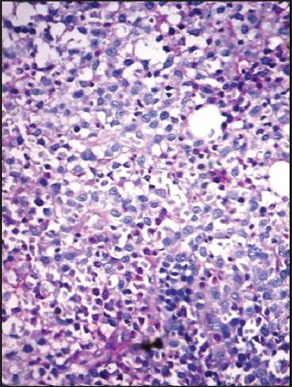

The clinicopathologic characteristics of all 14 patients with MM (13 newly diagnosed, 1 relapsed) are presented in Table 1. There were 11 males and 3 females with age range of 38-81 years (mean = 54 years, standard deviation = 10.7); and all were symptomatic at the time of evaluation. Eight (57%) were in Durie and Salmon Stage II, 5 (37%) Stage III and 1 (7%) in Stage I. Out of 14 cases, 10 (71.5%) presented with advanced lytic bone lesions, and two had organomegaly (one of which was de novo plasma cell leukemia). All, except one, had demonstrable light chain restriction (7 ‘ĸ’, 6 ‘λ’) by either IHC or biochemical assay techniques. Corrected serum calcium was found to be within normal range (≤11 mg/dL) in the majority of patients. On bone marrow evaluation, 10/14 (71%) cases showed an interstitial pattern of infiltration with or without focal nodularity; and 4 (29%) had packed marrow (diffuse pattern). Out of 14 cases, 10 (71%) cases were in Bartl's histologic Stage III (>50% tumor cells); and in 7 (50%), myeloma cells exhibited a high grade (blastic or pleomorphic) phenotype. Intracytoplasmic (Russell bodies) and intranuclear (Dutcher bodies) were noted in 11/13 patients; and in two intracytoplasmic crystalline inclusions were seen [Figures [Figures1a1a–g].

| Fig. 1f Hematoxylin and eosin stained bone marrow trephine sections showing a nodular pattern of infiltration by myeloma cells (×100)